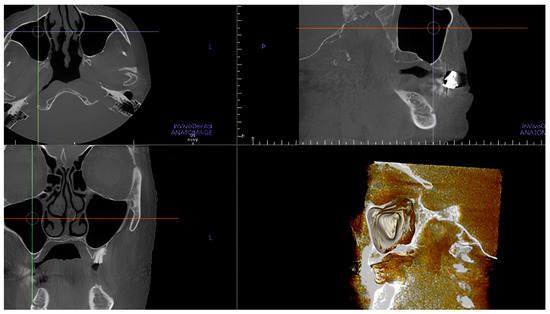

- The length of the arterial pathway in the mesiodistal dimension, on cross-section setting at 1 mm (Figure 2);

- The height of the maxillary bone crest in the cranio-caudal direction, on cross-section at the level of the first superior molar (Figure 3);

- The presence of the septa on cross-section (Figure 4);